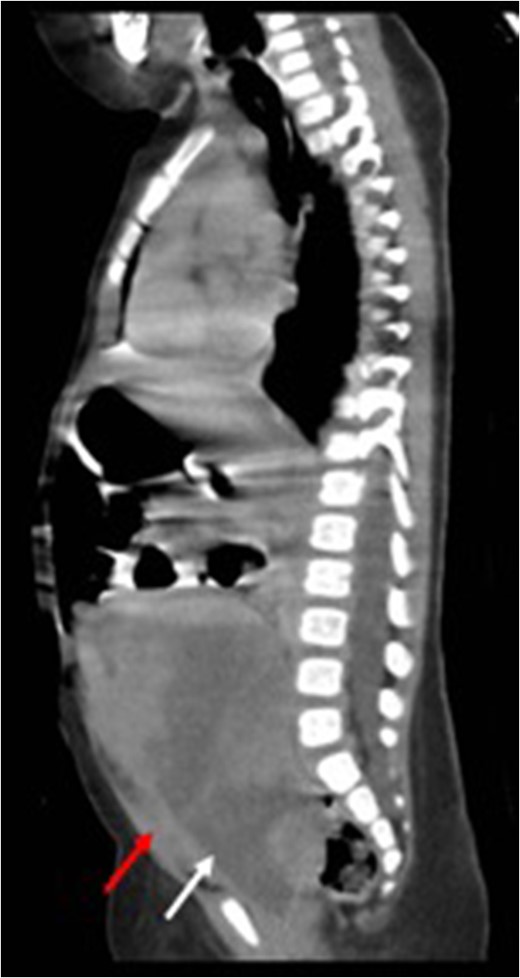

Post-treatment sagittal view (CT) with no evidence of recurrence arising from the uterus (red arrow) bladder.